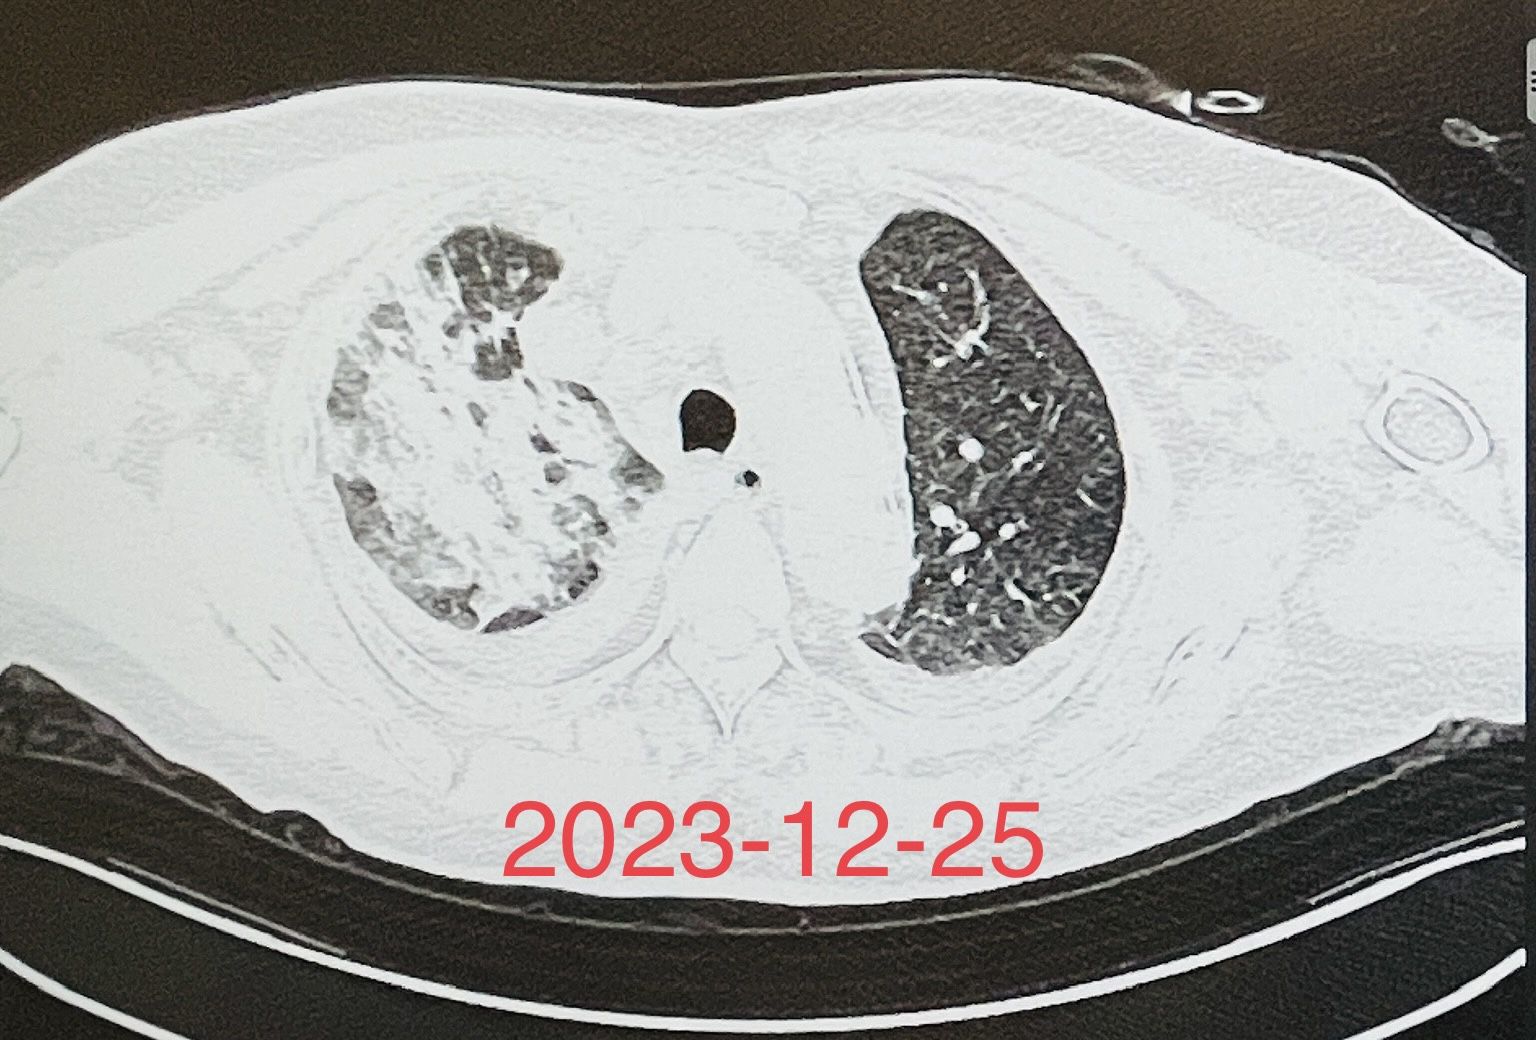

(图1)重症肺炎患者床旁气管镜检查及治疗前后的胸部X线片对比

这是收住呼吸RICU的一个混合感染,重症肺炎合并呼吸衰竭、心力衰竭的患者,经气管插管呼吸机辅助呼吸、床旁气管镜检查明确了病原菌,经积极有效的抗感染治疗,联合提高免疫、营养支持等综合治疗,以及呼吸重症监护室所有医护人员的精心护理,经积极抢救,患者的感染得到了有效控制,病情有了明显的改善。(图1)